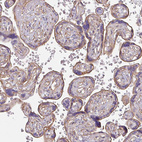

Immunohistochemistry analysis in human placenta and skeletal muscle tissues using HPA047541 antibody. Corresponding MYH10 RNA-seq data are presented for the same tissues.